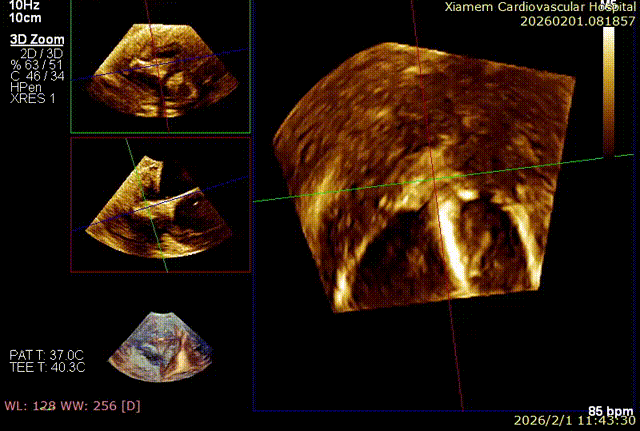

第一个夹子释放后,在前叶、隔叶间靠近中央区仍有残余反流,所以决定再植入一枚 6mm 夹合器。第二枚夹合器抓捕瓣叶过程中,受到第一枚夹合器影响,无法清晰的在 X-plane 切面上进行瓣叶捕获,因此改用 3D-MultiView 切面顺利抓捕,关闭夹合器后残余反流已经由术前极重度(4+)减小为轻中度(2+),手术过程流畅,手术结果完美。

3D-MultiView引导手术